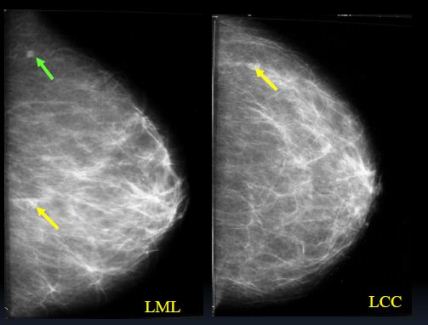

Kazuistika 3

Klientka odeslána do FN HK s Hi (CCB) ověřenými mikrokalcifikacemi

na rozhr.ZQ sin

- pouze v MDL projekci zachyceno 4mm ložisko v HQ

- popsáno jako intramam.LU, nemá korelát v KK

- Ve FN HK před výkonem zhotoveny KK a MDL projekce sin

- Ložisko v KK projekci (CCB Hi.duktální Ca)